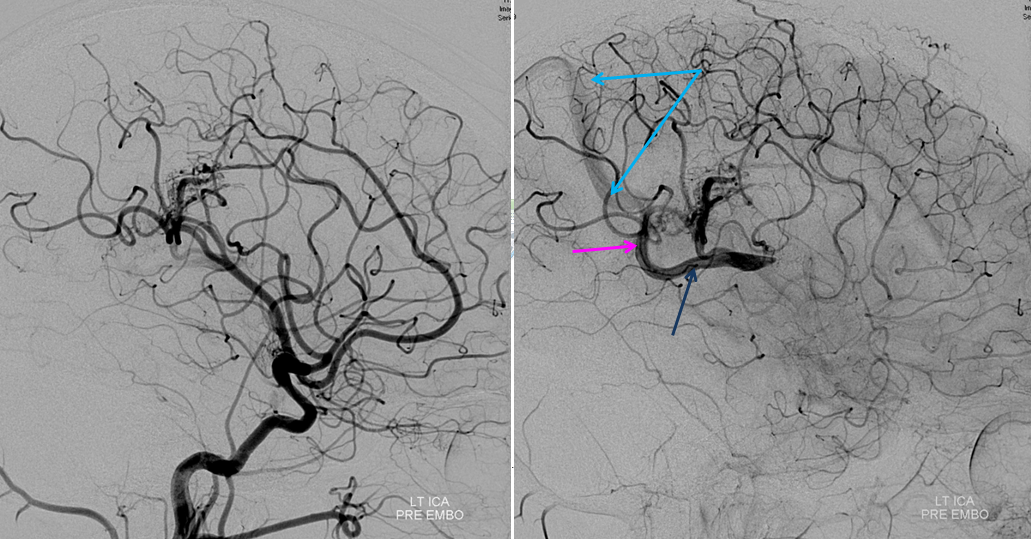

Following embolization, resection, recurrence (as frequently the case with childhood AVMs) and gamma-knife, things look good. Stereo, of course.

Following embolization, resection, recurrence (as frequently the case with childhood AVMs) and gamma-knife, things look good. Stereo, of course.